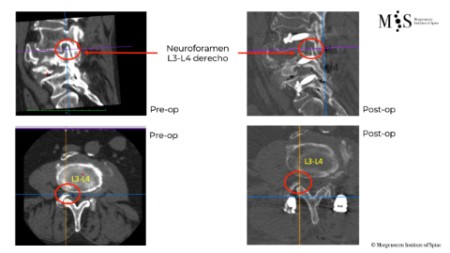

Comparación pre- y post-operatoria de una cifopastia cementada

Mujer, edad 55 años, Fractura aplastamiento derecho de L2

Antes 1

Después 1

Antes 2

Después 2